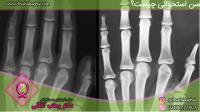

مطالب مفید: تشخیص سن استخوانی با رادیولوژی

قبل از انجام رادیوگرافی بایستی هرگونه اشیا فلزی را از بدن خارج کرد. باید توجه کرد که رادیوگرافی را نباید در هنگام بارداری استفاده کرد مگر با مجوز پزشک معالج در مواقع ضروری، بنابراین خانم ها باید کارشناس رادیولوژیست را از احتمال بارداری خود مطلع کنند. به جهت عکس برداری قسمت مورد مورد نظر را توسط اشعه ایکس روی فیلم قرار می‌دهند و اشعه بعد از عبور از پوست به بخش مورد نظر تابیده شده و به صفحه حساس برخورد کرده و رنگ این قسمت بعد چاپ به صورت سیاه دیده می‌شود ولی قسمت هایی که استخوان دارد اشعه عبور نمی‌کند و به صورت رنگ سفید دیده می‌شود مانند افتادن سایه روی دیوار.

بنابراین در یک عکس رادیوگرافی استخوان‌های محکم‌تر سفیدتر و آن‌ها که کمتر هستند کمرنگ‌تر می‌باشند. در واقع قسمت‌هایی که اشعه ایکس کاملا عبور می‌کند کاملا سیاه می‌باشند و بخش‌هایی که اشعه جزئی عبور می‌کنند خاکستری می‌شود مانند عضلات.

هنگامی که اشعه ایکس از بافت‌های بدن عبور کرده تصویری سیاه از این نواحی ایجاد و زمانی که با استخوان برخورد می‌کند، تصاویری سفید را در زیر صفحه مشکی نشان می‌دهد.

رادیوگرافی استخوان‌ها : با رادیوگرافی استخوان می‌توان بسیاری از شکستگی‌های، در رفتگی‌ها را ملاحظه نمود .